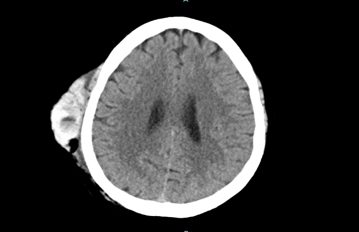

Upon arrival, CT of the head showed a large right frontotemporal scalp hematoma with hematocrit levels suggesting recent/active hemorrhage, no acute intracranial hemorrhage or extra axial collection, and left temporal encephalomalacia and gliosis likely related to prior treatment/ischemic insult with superimposed acute ischemia. CTA of the head/neck showed patent intracranial arteries without significant stenosis, occlusion, or aneurysm, a small amount of internal cerebral venous drainage, and a large superficial scalp hematoma over the right frontotemporal bone with active extravasation from the right superficial temporal artery. Both right and left internal carotid arteries showed no hemodynamically significant stenosis by NASCET criteria.

Image 3: CT Head Non-Contrast. Large right frontotemporal scalp hematoma